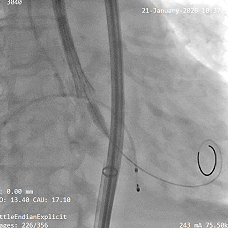

术中影像

根部造影

瓣叶活动差,可见明显反流,猪尾导管测量跨瓣压差约50mmHg

20mm球囊预扩

微腰微漏,左右冠均显影

造影确认瓣环与瓣膜位置

瓣膜0位初始定位释放,展开过程微微下移

全展开位造影评估

瓣膜呈直筒型,微腰,大弯侧约瓣下3mm,少量反流,冠脉显影

瓣膜无张力脱钩

植入后造影评估

瓣膜位置合适,可见少量反流

多角度造影评估

瓣膜形态可,冠脉显影,猪尾测量压差为0